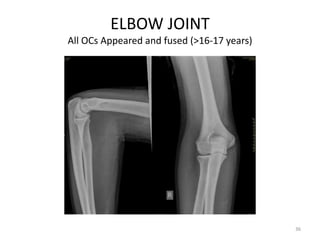

ELBOW JOINT

All OCs Appeared and fused (>16-17 years)

Elbow joint • Secondaryossification Centres : (3 bones; 6 Ocs) Capitulum (C) - appearance - 1 year of life Head of Radius (R)– appearance -4 to 5 years Medial Epicondyle (ME) Appearance – 5 to 6 years Fusion – 16 to 17 years Trochlea (T) – appearance – 9 to 11 years Olecranon Process of Ulna (OP) Appearance - 8 to 9 years Fusion- 16-17 years Lateral Epicondyle(LE) – 11 to 12 years Conjoint (Composite)Epiphysis (CE) [fusion of C+T+LE] Formation – 14 to 16 years Fusion – 16-17 years Note: Fusion of O.Centres at elbow joint is 16-17 years in male, 15-16 years in female 35

ELBOW JOINT All OCsAppeared and fused (>16-17 years) 36